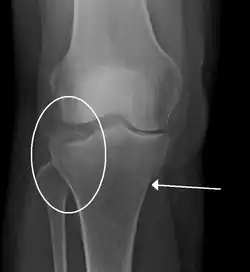

Lipohemarthrosis (presence of fat and blood from bone marrow in the joint space after an intraarticular fracture) seen on X-ray in a person with a subtle tibial plateau fracture -

Subtle tibial plateau fracture on an AP X ray of the knee -

A tibial plateau fracture seen on X-ray